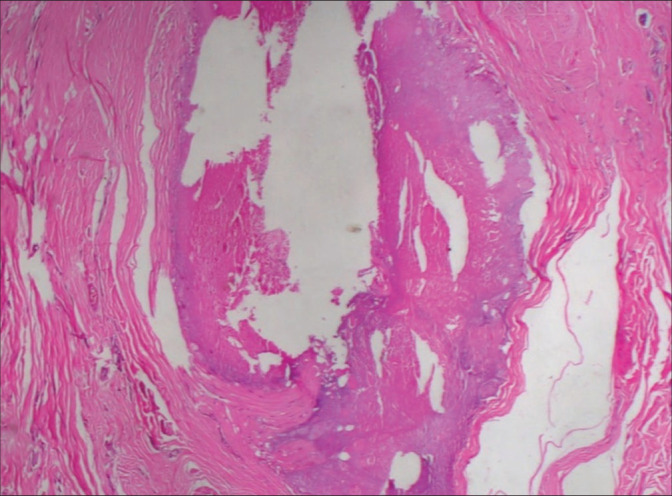

A 45-year-old man with an asymptomatic lesion on the scrotum since 25 years presented to the skin out patient department (OPD). There were multiple skin-colored to hyperpigmented nodules with areas of calcification on the scrotum. The mass measured 20 cm × 10 cm × 8 cm as a whole. Steatocystoma was clinically diagnosed and excision of the lesion was performed by a plastic surgeon. The mass was removed en masse and the removed specimen was measured to be 20 cm × 10 cm × 5 cm. On histopathological examination, the cysts showed epithelium resembling that of outer hair root sheath. Contents of the cysts were homogenous unlamellated keratin with focal calcification.